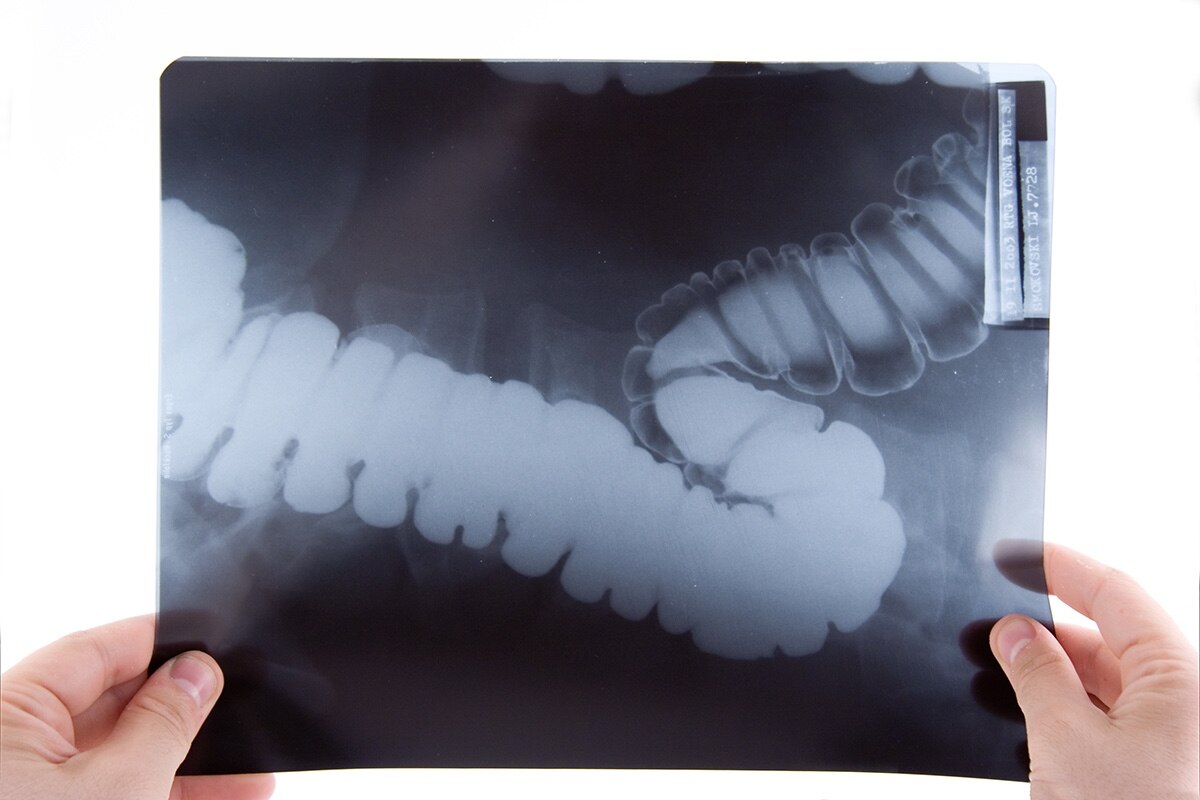

As discussed when evaluating clients for GERD, an ambulatory esophageal reflux monitoring test can also be used to determine if a client has a hiatal hernia. Additionally, a barium esophagram or swallow test is another way radiologists and providers can diagnose hiatal hernias after the client swallows the contrast-enhanced barium to easily visualize the anatomy and structures of the GI tract in radiographic images.